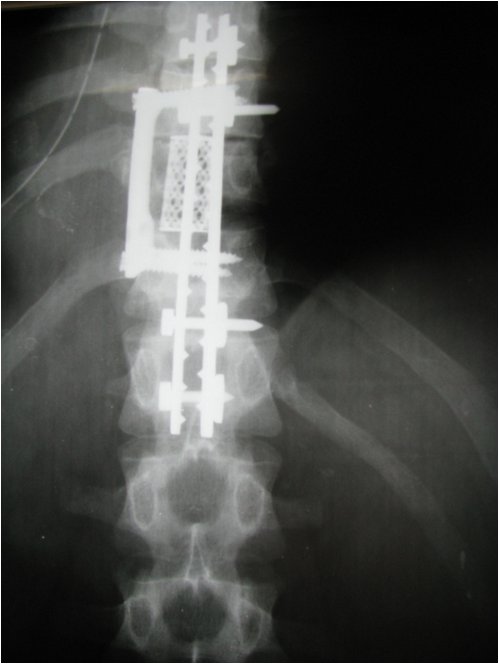

Перелом l 2

Перелом l 2 125 фото